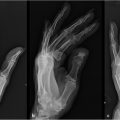

Standard 3 view radiographs are obtained for all patients with traumatic etiology. These are also used selectively in tumor extirpation, thermal injuries, and infectious complications as there may be bone involvement. Other imaging modalities such as computed tomography, magnetic resonance imaging, and angiography may be of value in select cases where bone reconstruction may accompany soft-tissue coverage or free tissue transfer is being considered. Photographic documentation of the original and subsequent examinations is helpful for providing a more objective basis for comparisons over time and among providers.

Understanding the anatomic nature of the defect and its location will provide the surgeon the key elements in choosing an appropriate reconstructive option for soft-tissue coverage of hand and upper extremity defects. Table 25‑3 describes four anatomic sites or zones of injury requiring soft-tissue reconstruction. Alternatives for care for each of these sites are listed in the right column. The actual reconstruction chosen will depend on the volar or dorsal nature of the defect as well as the degree of tissue loss.